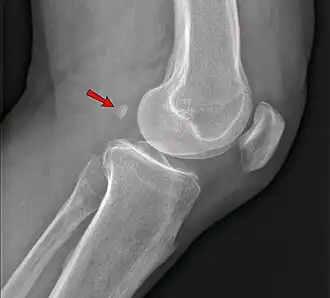

The fabella is a small sesamoid bone found in some mammals embedded in the tendon of the lateral head of the gastrocnemius muscle behind the lateral condyle of the femur. It is an accessory bone, an anatomical variation present in 39% of humans.[1][2] Rarely, there are two or three of these bones (fabella bi- or tripartita). It can be mistaken for a loose body or osteophyte. The word fabella is a Latin diminutive of faba 'bean'.[3]

"The fabella can lead to posterolateral knee pain either due to cartilage softening (chondromalacia fabellae) or other osteoarthritic changes on its articular surface."[7]